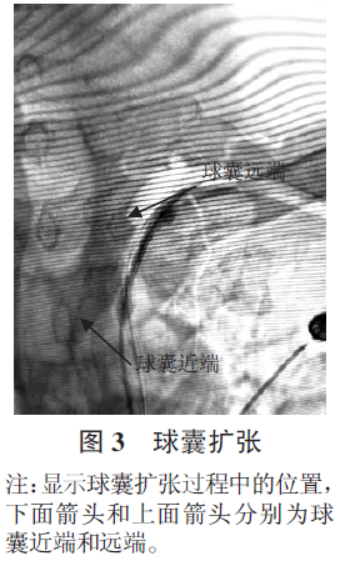

造影后每日给予患者阿司匹林肠溶片100 mg、硫酸氢氯吡格雷75 mg 进行抗血小板聚集治疗,给予阿托伐他汀钙片20 mg 进行稳定斑块治疗。服用1 周药物后在局麻下行球囊成形术、支架置入术:6F导引导管系统置于左侧锁骨下动脉开口处,再次造影测量狭窄段长度约1.8 mm,微导丝顺利通过狭窄段,到达左侧肱动脉。把PTA 球囊交换到狭窄部位,再次造影明确球囊位置(图3)后缓慢充盈球囊,扩张狭窄部位。